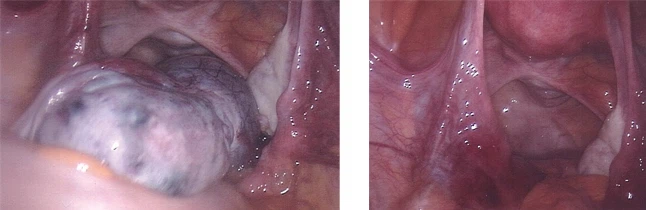

복강경하 난소 낭종 절제술

배꼽 부위 1 cm 가량의 구멍을 뚫고 내시경을 넣어 모니터를 보면서 하복부에 2~3개의 5mm 구멍을 통해 수술 기구를 삽입, 조작하여 수술하는 방법으로 떼어낸 난소낭종은 구멍을 통하여 꺼내게 됩니다. 개복을 하지 않으므로 회복이 빠르며 흉터가 거의 남지 않습니다.